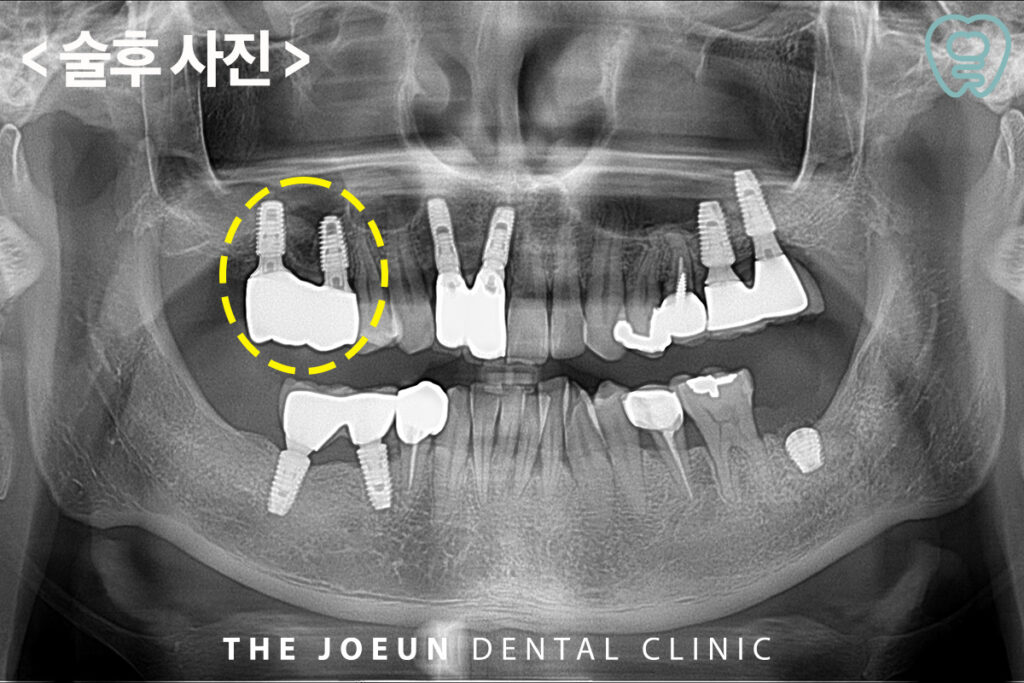

환.자분께서는 오른쪽 어금니 쪽에 가끔 양치하실 때 피가 나신다며 내원해 주셨는데요. 구강 내 전반적으로 치주염이 진행되고 있는 상태였고 특히 말씀해 주신 오른쪽 위 어금니 부위와 왼쪽 아래 어금니 쪽은 염증이 잇몸뼈를 녹이고 있는 것이 관찰되었습니다. 따라서 위쪽의 경우에는 상악동 거상술을 동반한 임플란트 식립을, 아래쪽은 발치 후 식립을 진행하기로 하였습니다.

오른쪽 위 어금니를 발치한 후의 모습입니다. 크게 자리 잡고 있었던 염증 조직들까지 말끔히 제거된 모습인데요.

이후, 상악동 거상술을 동반한 임플란트 식립을 진행하였습니다.

상악동 거상술의 방법은 치조정 접근법과 측방 접근법으로 나뉘어 일반적으로 이식을 해야 하는 뼈의 양이 적을 때는 치조정 접근법을, 뼈이식의 양이 많을 때는 측방 접근법을 주로 사용합니다. 위 환.자분은 치조정 접근법을 통하여 뼈이식을 진행하였는데요.

위쪽에는 뼈이식을 동반한 임플란트 식립을 진행하였기 때문에 기존의 잇몸뼈와 충분히 융합될 수 있는 기간을 기다려주어야 하는데요. 그동안 왼쪽 아래의 임플란트 식립을 진행하였습니다. 신경관과의 거리가 짧아 길이가 짧은 인공치근을 식립하게 되었습니다.

이후, 오른쪽 위 임플란트의 보철까지 마무리를 하였습니다.

마지막으로 왼쪽 아래 최종 보철물까지 완료하였습니다.